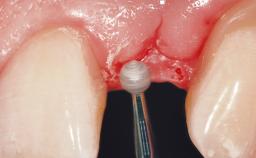

Dr. Gallucci is the Chair of the Department of Restorative and Biomaterial Siences at Harvard School of Dental Medicine. ITI Fellow since 2004, Chair of the ITI Scholarship Center at Harvard.

ITI Study Club UIC Chicago - Lecture with Dr. German Gallucci - “Implant-Prosthodontic Integration in the Esthetic Area”